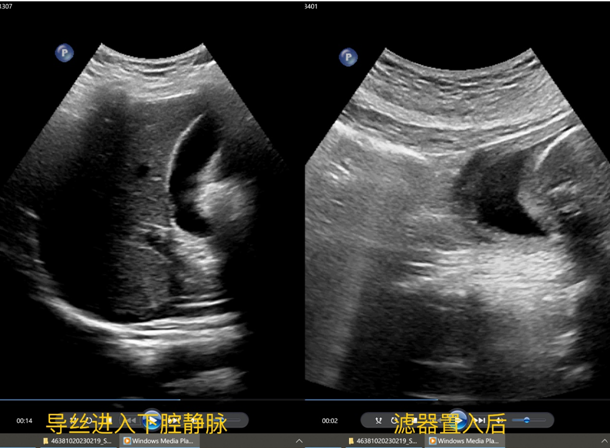

手术过程中,患者取平卧位,右侧腹股沟常规消毒铺巾,2%利多卡因5ml局部麻醉,右侧股静脉穿刺,置入导丝,确认导丝进入下腔静脉,顺导丝置入鞘管,拔出导丝,确认鞘管顶端位于肾静脉水平以下、汇合部以上的下腔静脉腔内,以顶杆推入滤器至鞘管顶端,超声定位,释放滤器,超声观察:滤器打开顺利,位置正常,形态良好,彩色血流示:滤器内血流通畅。